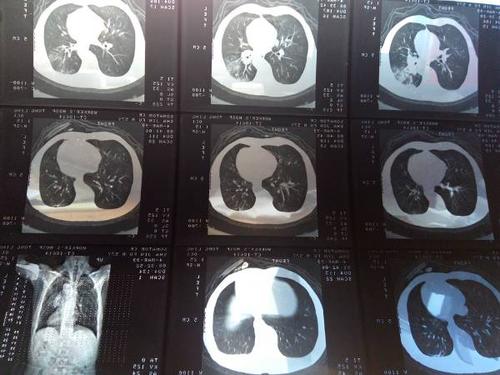

术前肺部增强ct片

肺癌ct图片

肺部ct图片

肺部肿瘤ct图片

肺脓肿ct图片

肺气肿的ct图片